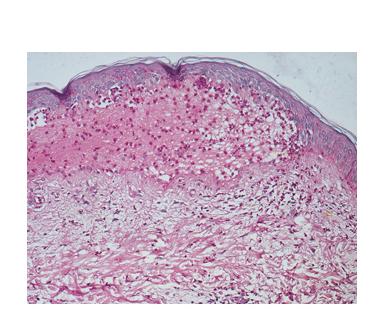

Histopathology.

In early lesions, papillary dermal edema in combination with a cell-poor or cell-rich perivascular lymphocytic and eosinophilic infiltrate is present. The blister arises at the dermal-epidermal junction . In the cell-rich pattern, which correlates clinically with blisters arising on erythematous skin , eosinophilic papillary abscesses may develop with numerous perivascular and interstitial eosinophils intermingled with lymphocytes and neutrophils in the superficial and deep dermis. Early lesions may have the histologic features of eosinophilic cellulitis (Well’s syndrome). Eosinophilic spongiosis may occur. The cell-poor pattem is observed

when blisters develop on relatively normal skin , in which there is usually a scant perivascular lymphocytic infiltrate with few eosinophils, some scattered throughout the dermis and others near the epidermis. The blister contains few inflammatory cells. Epithelial migration and regeneration may result in an intraepidermal split in older blisters. Similar to pemphigus vegetans, a hyperplasia of the epidermis, subepidermal bullae, and accumulations of eosinophils and lymphocytes may be seen.